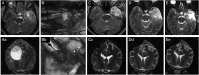

With the median survival of 14.6 months following best available standard of care, malignant gliomas (MGs) remain one of the biggest therapeutic challenges of the modern time. Although the last several decades have witnessed tremendous advancement in our understanding of MG and evolution of many successful preclinical therapeutic strategies, even the most successful preclinical therapeutic strategies often fail to cross the phase I/II clinical trial threshold. One of the significant, but less commonly discussed, barriers in developing effective glioma therapy is the lack of a robust preclinical model. For the last 30 years, rodent orthotopic xenograft models have been extensively used in the preclinical setting. Although they provide a good basic model for understanding tumor biology, their value in successfully translating preclinical therapeutic triumph into clinical success is extremely poor. Companion dogs, which share the same environmental stress as their human counterparts, also spontaneously develop MGs. Dog gliomas that develop spontaneously in an immunocompetent host are very similar to human gliomas and potentially provide a stronger platform for validating the efficacy of therapeutic strategies proven successful in preclinical mouse models. Integrating this model can accelerate development of effective therapeutic options that will benefit both human subjects and pet dogs.